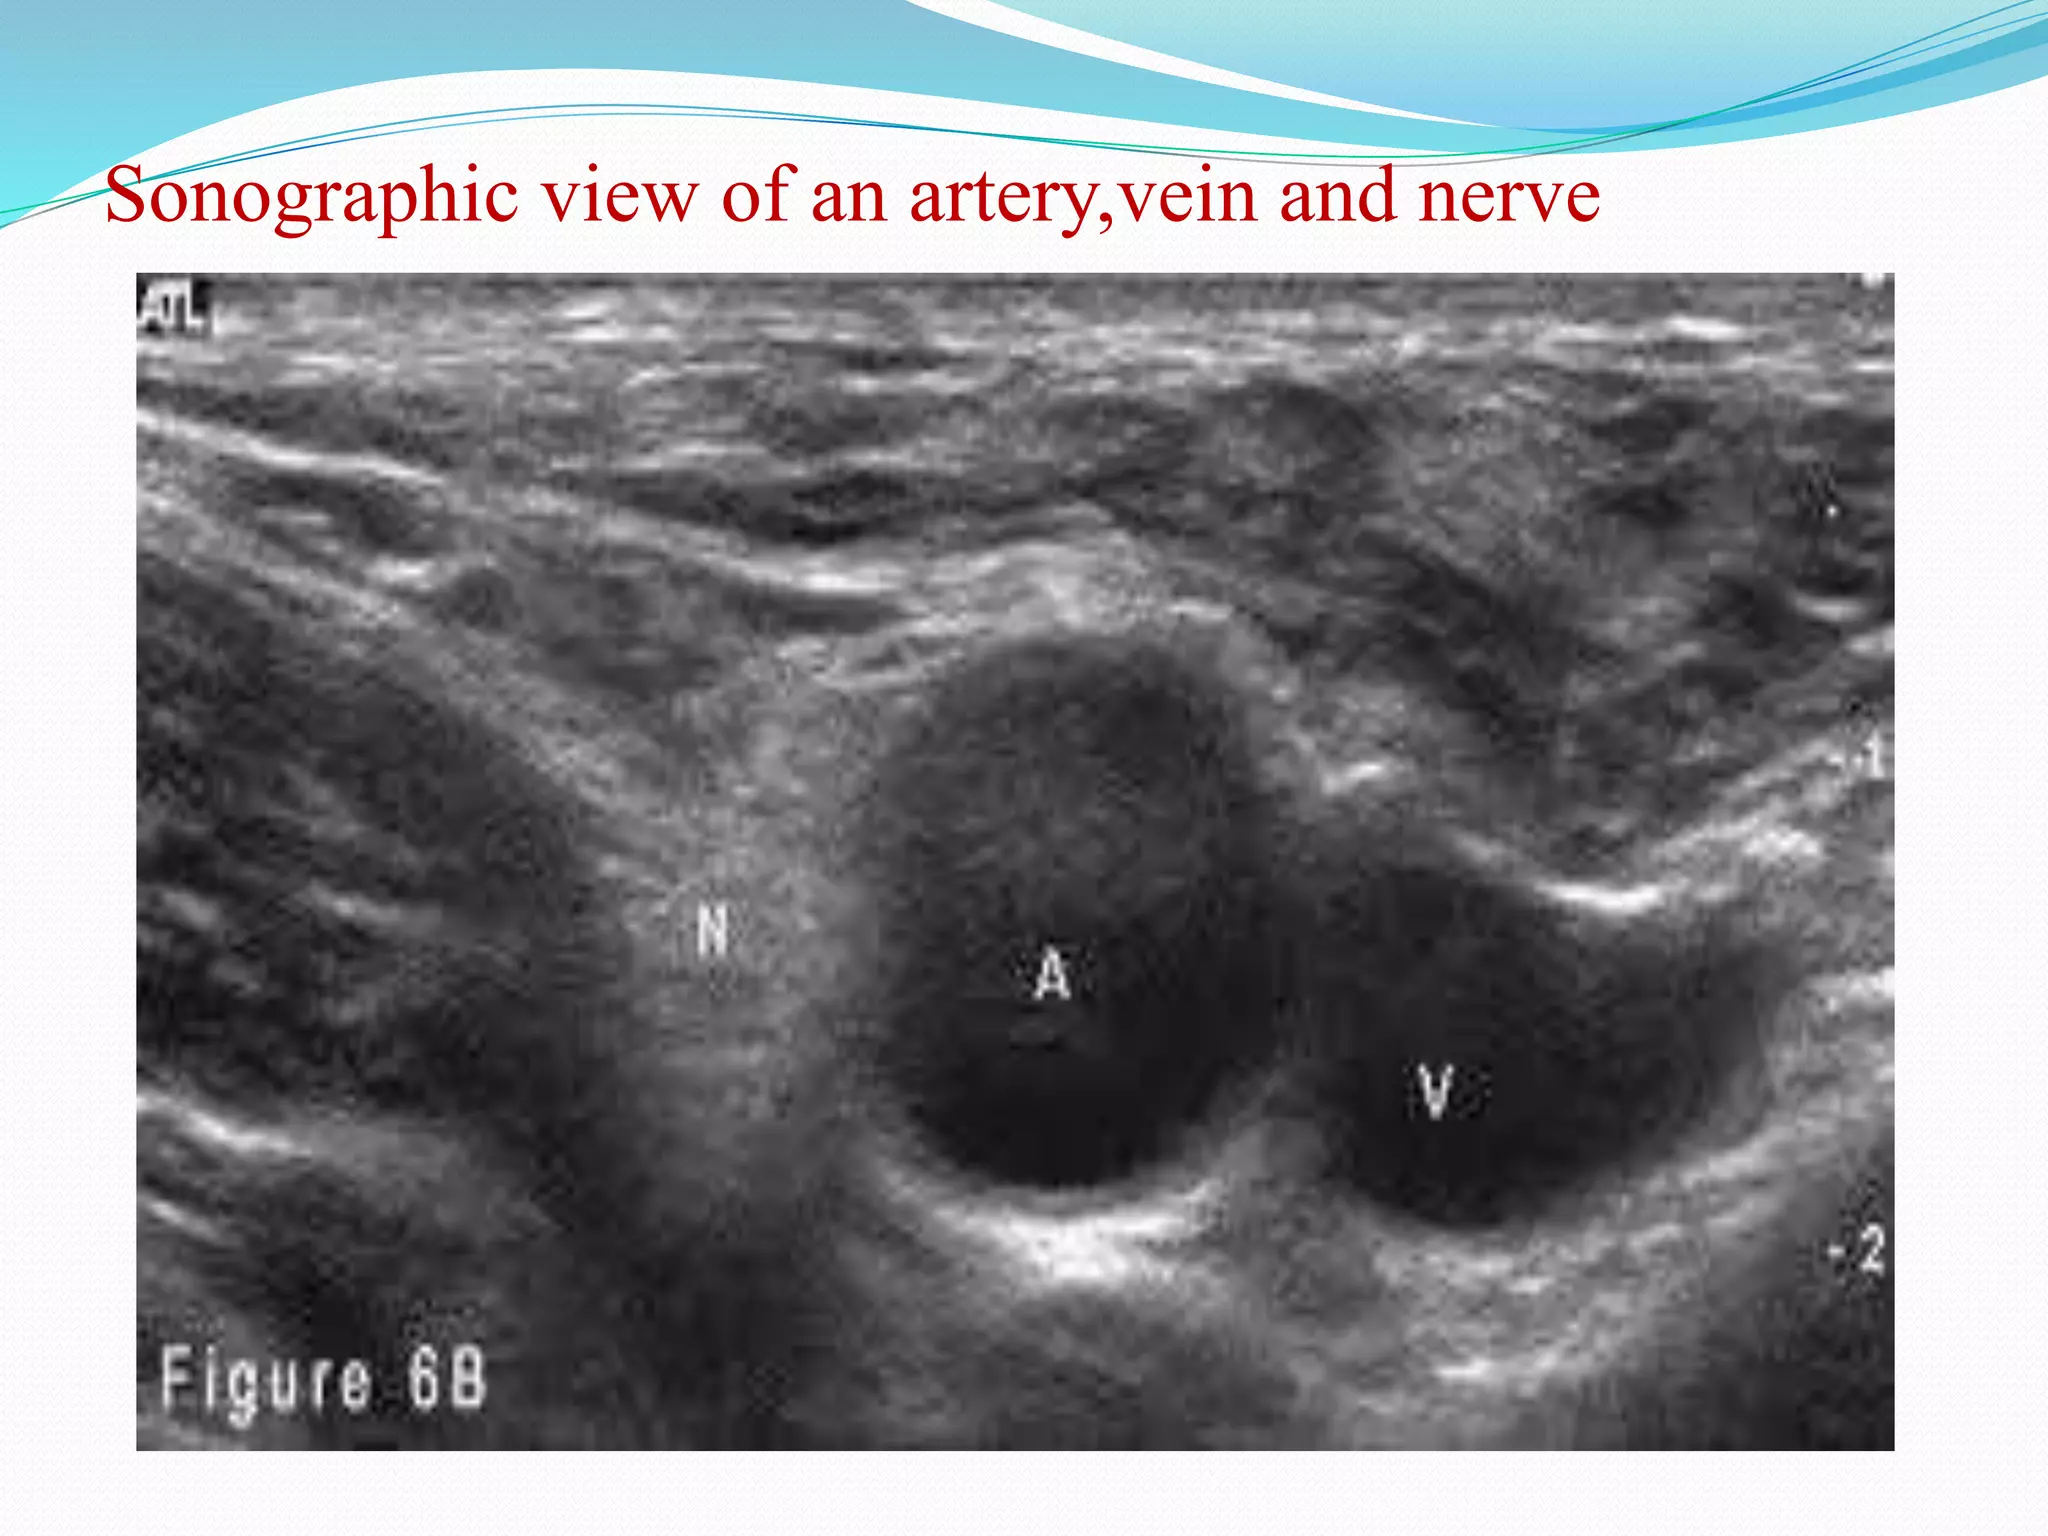

This document provides an overview of brachial plexus anatomy and techniques for brachial plexus nerve blocks. It begins with a description of the brachial plexus formation from cervical and thoracic nerve roots and its branching pattern. Four main approaches for brachial plexus nerve blocks are described: interscalene, supraclavicular, infraclavicular, and axillary. Details are provided on the anatomy and techniques for performing interscalene and supraclavicular brachial plexus blocks. Ultrasound guidance is discussed as an advancement which allows real-time visualization of needle and nerve. Complications are also summarized.